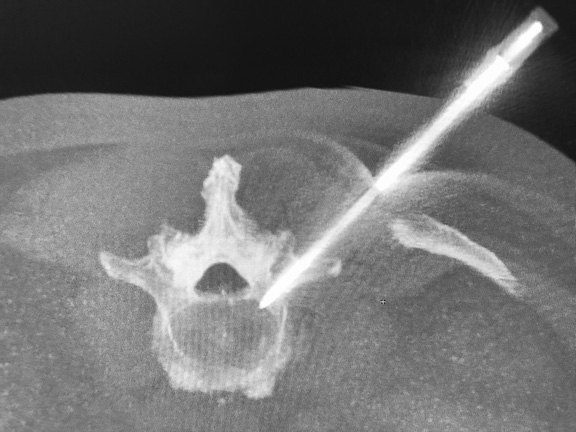

Dr. Massari, a member of the UMass Neurointerventional Radiology Group performed a transpedicular lumbar vertebra biopsy on a patient referred by a local practitioner. Pictured is the radiology team from left to right: Lisa Laprade, procedural technician, Jayne Roose, RN, Kalyn Dhroso, PA, Francesco Massari MD, Amin Chaoui, MD, Danielle McHugh RT CT.